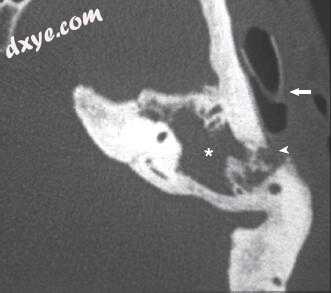

图-11. 影像学表现为左侧岩尖炎。 A,颞骨骨骼计算机断层扫描显示左颞骨岩尖炎。注意岩骨顶端的浑浊与骨质隔膜(星号)的破坏。在这个对比研究中也可以看到颈动脉管的裂开和岩骨颈动脉的狭窄(箭头)。 B,轴位非对比增强T1加权磁共振成像(MRI)显示乳突浑浊(星号)。与右侧看到的亮脂肪信号相比,左侧岩尖也是不透明的(箭头)。注意左侧颈内动脉狭窄口径(ICA;短箭头)与右侧ICA(箭头)相比。 C,轴向造影增强T1加权MRI在左侧岩尖处显示低信号,周边对比度增强(黑色箭头)与炎症一致。注意左侧ICA的窄口径(短箭头)与右侧的ICA(箭头)相比较。 D,冠状位造影增强T1加权MRI在左侧岩尖部显示低信号,周边对比度增强(黑色箭头)。注意增强毗邻岩尖的硬脑膜和颞叶(白色箭头)。 E,治疗前患者的MR血管造影(MRA)显示左侧岩石ICA变窄(箭头)。 F,随访MRA显示缩小后的ICA正常口径(箭头)。